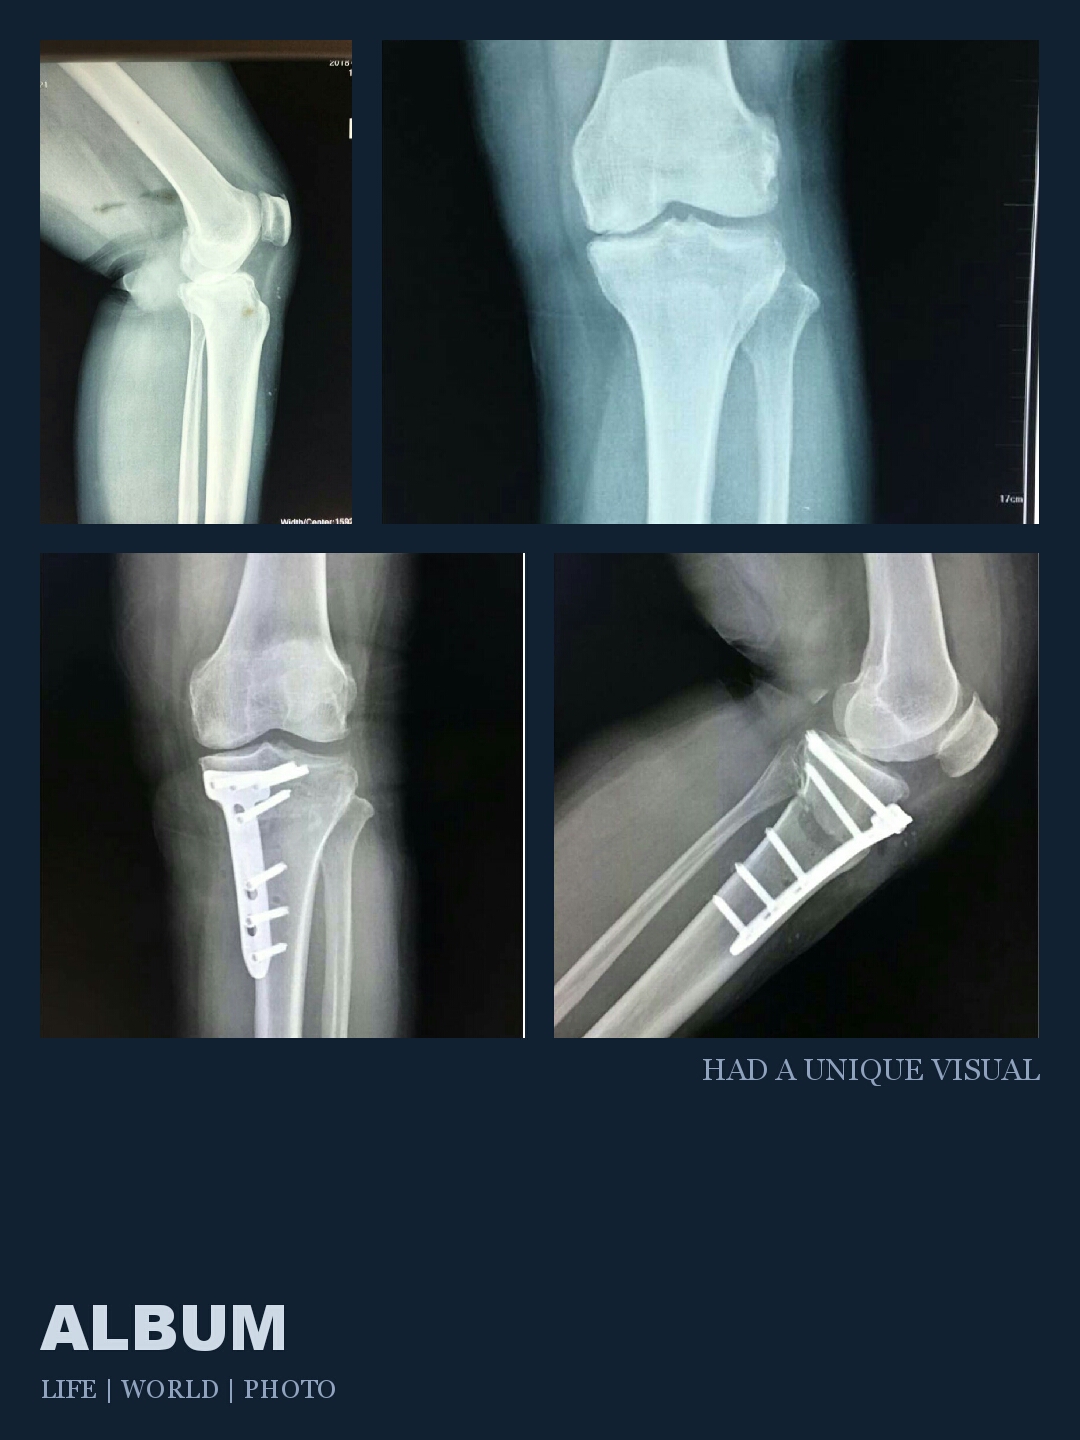

骨二科成功完成一例脛骨高位截骨治療膝關(guān)節骨性關(guān)節炎手術(shù)

骨二科近日獨立完成我院首例脛骨高位截骨(HTO)治療膝關(guān)節骨性關(guān)節炎手術(shù)?;颊吲?0歲,膝關(guān)節內側疼痛4年余,保守治療無(wú)效。董建國主任帶領(lǐng)全科人員討論病情并制定了周密的手術(shù)計劃及術(shù)前設計。手術(shù)主要原理是矯正下肢力線(xiàn),解放膝關(guān)節內側室間的壓力,使退變關(guān)節軟骨再生,延緩膝關(guān)節退變時(shí)間,延長(cháng)膝關(guān)節使用壽命。適應癥為:年齡小于65歲,脛骨內翻畸形,外側間室完好。手術(shù)優(yōu)點(diǎn):保留膝關(guān)節所有正常結構,術(shù)后可早期下床活動(dòng),恢復快,相對膝關(guān)節置換保留了良好的本體感覺(jué),具有更好的穩定性。